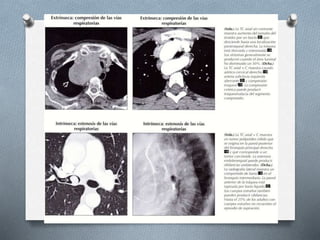

Obstrucción de vías respiratorias:

- Extrínsecas e intrínsecas.